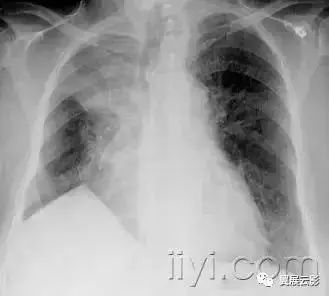

五十六、气胸和张力性气胸

病理:气胸指胸膜腔内出现气体。包括自发性、外伤性、诊断性和张力性气胸。张力性气胸是指胸膜腔内气体积聚,具有一定的压力。正常情况下,以此肺会完全压缩塌陷,而在顺应性减低的肺,可以保持膨胀不全。

平片和CT:在胸片上,可以看到脏层胸膜边,图55,除非气胸量很少,或者胸膜边缘与x线不呈切线位。张力性气胸可以出现明显的纵隔移位和/或一侧膈压低。一些非张力性气胸也可以出现纵隔移位,这是由于病变侧胸膜腔内压力达到大气压,而健侧胸膜腔压力为负造成的。